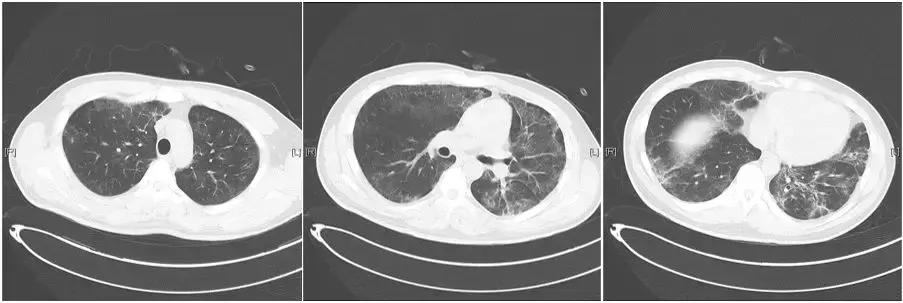

血常规:WBC 5.06×10^9/L,N 82.0%,HGB 141g/L(此后复查为90g/L),PLT 123×10^9/L。血生化:ALT 137U/L,AST 462U/L,CK 18642U/L,CKMB 536U/L,Cr 109μmol/L(此后复查为203μmol/L),K 3.29mmol/L,Na 123.9mmol/L。血气分析(无创通气,EPAP 8cmH2O,FiO2 100%):pH 7.44,PCO2 31mmHg,PO2 35mmHg,HCO3- 21.1mmol/L,Lac 1.3mmol/L。PCT:22.0ng/ml。血、尿肌红蛋白均为阳性。胸部CT【图1】:双肺多发磨玻璃,双下肺大片实变影,纵隔气肿、双侧少量胸腔积液。

【图1】入院时胸部CT